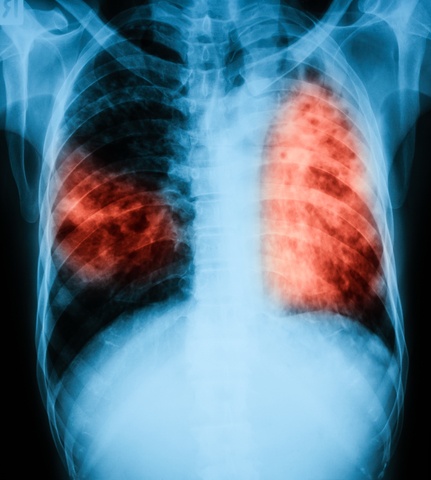

Imaging tests are used to look at your lungs after a positive skin test, normally an x-ray or CT scan.

These tests allow doctors to see into your lungs and look at if and how TB has affected your lungs and help doctors determine the best route of treatment for you.